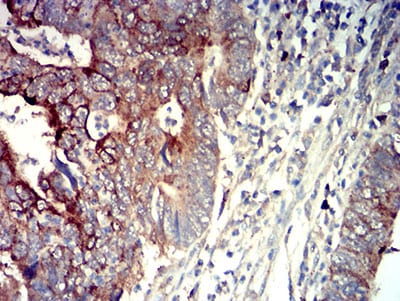

Immunohistochemical analysis of paraffin-embedded human lung cancer tissues using P2RY14 mouse mAb with DAB staining.

-

Immunohistochemical analysis of paraffin-embedded human rectum cancer tissues using P2RY14 mouse mAb with DAB staining.